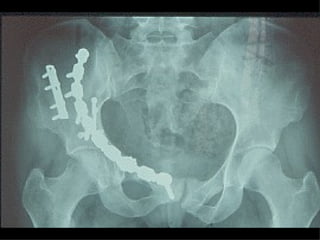

La lesione dell’apparato muscolo scheletrico che richiede  in ogni caso  un trattamento chirurgico con  priorità   assoluta  è la rottura dell’anello pelvico , che comporta una emorragia severa nel retro peritoneo e nella cavità peritoneale.

Immediata riduzione e fissazione del bacino

Se la risposta emodinamica a questo trattamento è buona il paziente verrà monitorato e potrà essere programmato un successivo intervento di osteosintesi definitiva

Angiografia e/o packing pelvico Se il paziente rimane instabile